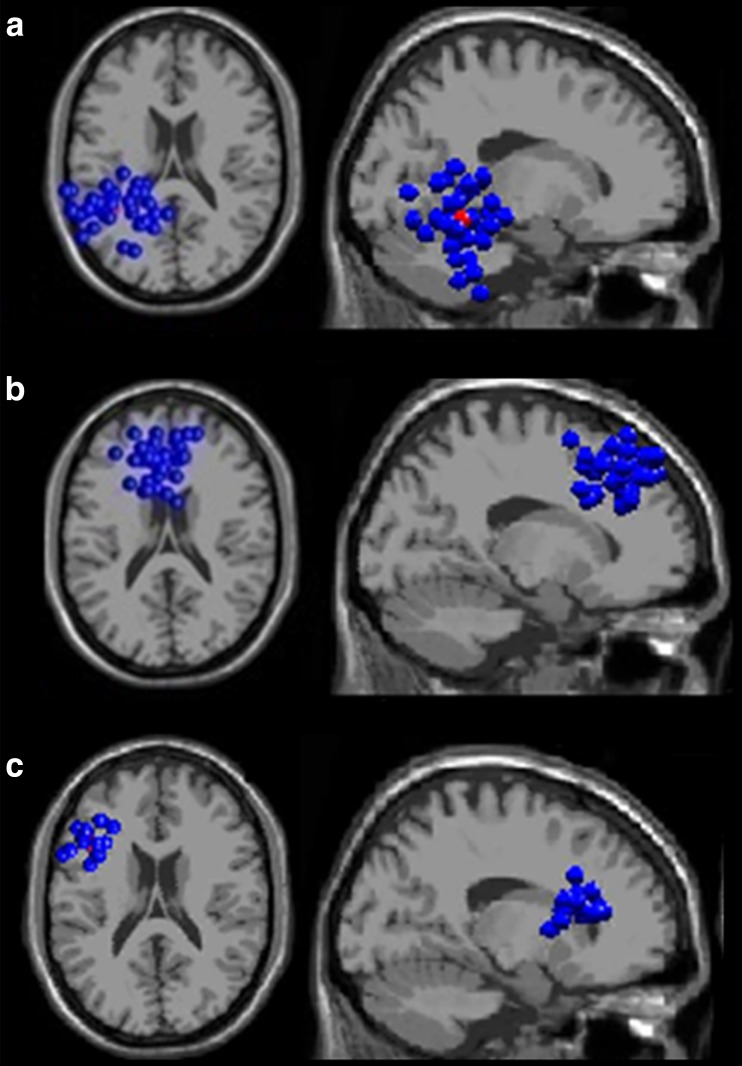

As a result of the independent component clustering, 16 clusters of independent sources were identified. Their exact localizations are shown in Table 1. Group effects of spectral power were revealed in three clusters of sources, localized in LTmp, ACC and LDLPFC (localizations of each cluster’s sources are presented in Fig. 1). An additional group*valence interactive effect was found in the LTmp region.

Fig. 1.

Localization of the three clusters of equivalent source dipoles (blue points denote dipoles of constitutive independent components as localized in each subject, while the red one denotes the cluster centroid); (a) the left temporal cortex (LTmp) cluster, top and saggital view; (b) the anterior cingulate cortex (ACC) cluster, top and saggital view; (c) the left dorsolateral prefrontal cortex (LDLPFC) cluster, top and saggital view. Clusters were modelled with the use of the MNI standard brain template